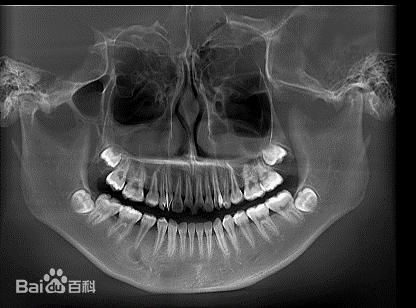

口腔CBCT是Cone beam CT的简称,大家可能也不是很熟悉,其原理是X线发生器以较低的射线量围绕投照体做环形DR(数字式投照),CBCT的投影数据是二维的,重建后直接得到三维图像。

老裘找了一张做完CBCT的影像图,相信大家看后就能大致明白了。

首先是临床应用。口腔CBCT可获得高质量颌、口腔全景图像和各方位断层图像。目前口腔CBCT广泛应用于空腔颌面外科、正畸科、正颌外科、种植科、牙体牙髓科、牙周科等,为临床多学科诊断、评估提供了更直观准确的影像资料,从而提高了手术和治疗的安全性和成功率。